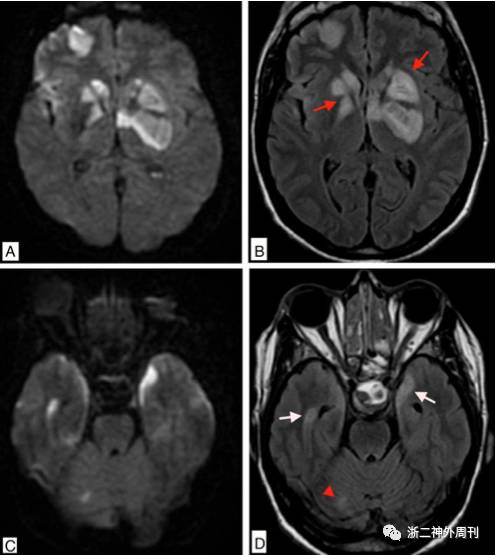

患者出院后回家,症状并无明显改善,2017.05.18日起出现头痛加重,神志淡漠,嗜睡,逐渐加重,2017.05.22再次就诊我院神经外科,查头颅CT提示蝶鞍扩大,鞍区高密度灶(图1B)。垂体磁共振增强提示鞍区占位伴出血。磁共振DWI相提示双侧额叶内侧及扣带回皮层下高信号,弥散受限,考虑急性脑梗塞(图2)。垂体激素提示:游离T3(FT3)1.74pmol/L↓、游离甲状腺素FT45.57pmol/L↓、总甲状腺素TT440.3nmol/L↓、皮质醇(8am)12.4nmol/L↓、黄体生成素<0.3IU/L↓、卵泡刺激素0.6IU/L↓。生长激素1.75ng/ml, IGF-1 79.3ng/ml↓,PRL79.3mIU/L正常。心电图提示前壁ST段抬高,肌钙蛋白-T 0.021ng/ml↑,空腹血糖14.0mmol/l↑,早餐后血糖16.2mmol/l↑。急诊拟“垂体腺瘤卒中,额叶梗塞,糖尿病”收住入院。

图2. A. 垂体增强磁共振提示鞍区占位,考虑垂体大腺瘤,伴双侧额底片状强化;B. DWI序列提示双侧额叶底部内侧,扣带回前部皮层和皮层下弥散受限,提示脑梗塞急性期。